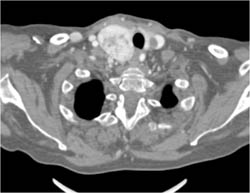

Splenic Artery Aneurysm